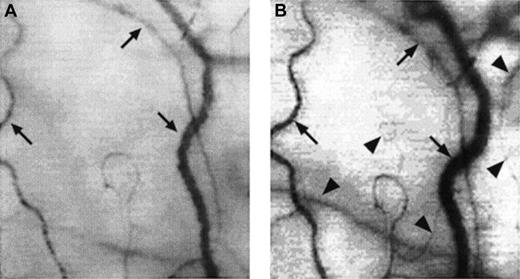

Two frame-captured images showing microvascular changes during crisis resolution in the same SCD patient.

Optical magnification, × 4.5; onscreen magnification, × 125. Focusing was aimed at the same location during crisis and crisis resolution, with the same vessel serving as its own reference baseline. (A) During crisis, there is significant reduction in vessel diameter and disappearance of capillaries and arterioles, resulting in extreme avascularity. The arrows point at the three vessels targeted for longitudinal comparison during crisis resolution. (B) An increase in vessel diameter and reappearance of capillaries and arterioles occur during crisis resolution. The vessels indicated by the arrows show a significant increase in vessel diameter. In addition, capillaries and arterioles (arrowheads) reappear during crisis resolution.

These acute microvascular abnormalities were transient, and the microvasculature reverted to steady-state values after resolution of painful crisis (postcrisis). In reality, normal steady-state values are comparable to postcrisis values made 1 month after crisis resolution. During crisis resolution, reemergence of capillaries and arterioles (reperfusion) was observed in all patients (Figure 4B).